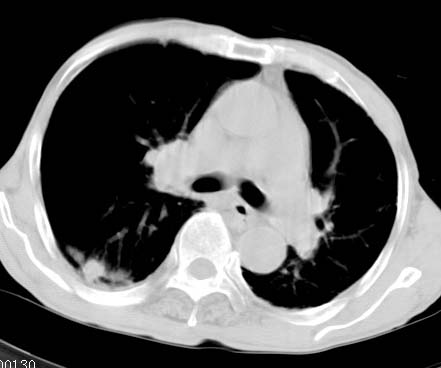

男性病人 81岁 胸痛 咳嗽2月 2周前提示右下肺感染.

今片ct示双肺多发结节影 可以这样诊断吗?1\双肺感染性病变 结核待排.

2\双肺纤维硬结灶,左肺肺气肿.

3\肺间质纤维化,胸膜肥厚粘连.

两肺转移瘤可能性大

两非继发性肺结核纤维硬结型

两非慢性支气管炎非大炮

两非胸膜广泛肥厚

右侧胸腔极少量积液。

此病人,诊断如下:1、双肺陈旧结核,活动与否请结合临床及其它检查。2、慢支炎,肺气肿,并双肺

多发肺大泡。3,胸膜肥厚、粘连。4、右下肺多个小结节,转移瘤不能除外。

不支持肺间质纤维化。

两肺上叶见多发索条状高密度影,右肺下叶见片状、结节状高密度影,两肺体积增大,胸膜下区见囊状低密度影、内有分隔结构。左肺下叶见网格影。两侧胸膜见增厚影。诊断:两肺继发性肺结核。慢性支气管炎合并感染。肺气肿。肺间质纤维化。胸膜增厚。